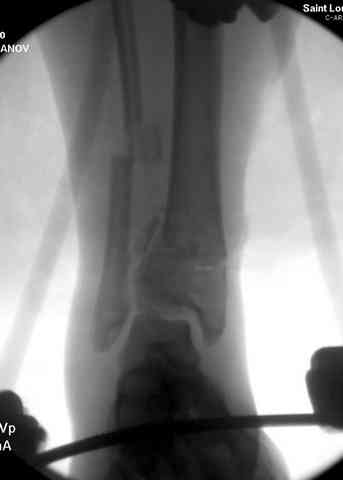

В первые часы после поступления больным экстренно накладывается простой фиксатор из двух поперечно проведенных стержней или сооружается "Delta

Frame" в зависимости от места локализации, и проводится дистракция.

Преимуществ у временного фиксатора много, во первых больной независим, если по другим показаниям нет необходимости находиться в стационаре, то больной может быть выписан домой с возможностью в амбулаторных условиях оценивать состояния мягких ткани на готовность к операции.

Наружным фиксатором обеспечивается длина конечности, предупреждается вторичное сокращение мягких ткани, что является немаловажным фактором для заживления послеоперационных ран. Без фиксатора сокращенные мягкие ткани легко травмируется во время манипуляций, трудно будет провести репозицию, ухудшается местное кровообращение и сохраняется посттравматический отек.

Здесь выставлена пара случаев перелома пилона, оба

случая леченные этапным наружным фиксатором.